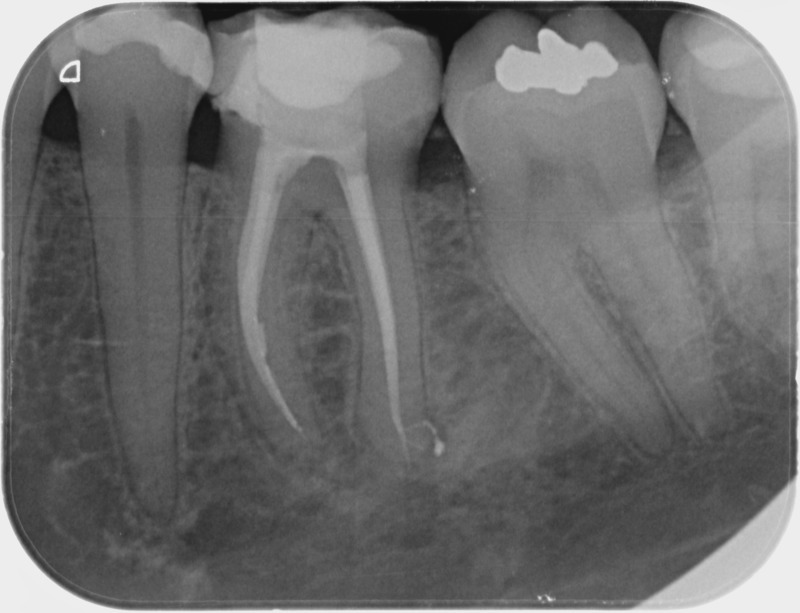

• Reprise de traitement endodontique : La manœuvre consiste à retourner à l’intérieur des racines d’une dent déjà traitée. Il arrive occasionnellement qu’une nouvelle inflammation se déclare suite à une reprise de carie ou une fracture de la dent, ou si le premier traitement endodontique est incomplet. Après s’être assuré que la dent lésée était conservable, il convient de désinfecter de nouveau le réseau canalaire parfois très complexe. La nouvelle obturation des canaux devra être protégée aussi rapidement que possible pour éviter une éventuelle contamination bactérienne.

Avant